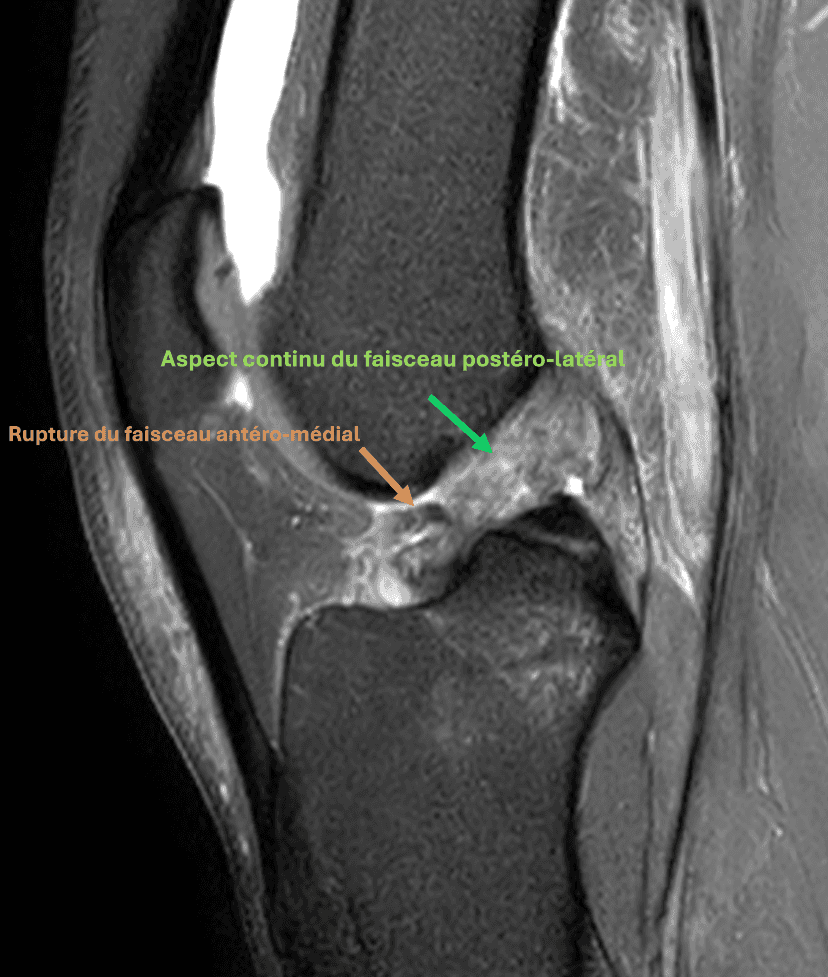

Rupture partielle du ligament croisé antérieur aux dépens du faisceau antéro-médial, avec aspect continu du faisceau postéro-latéral.